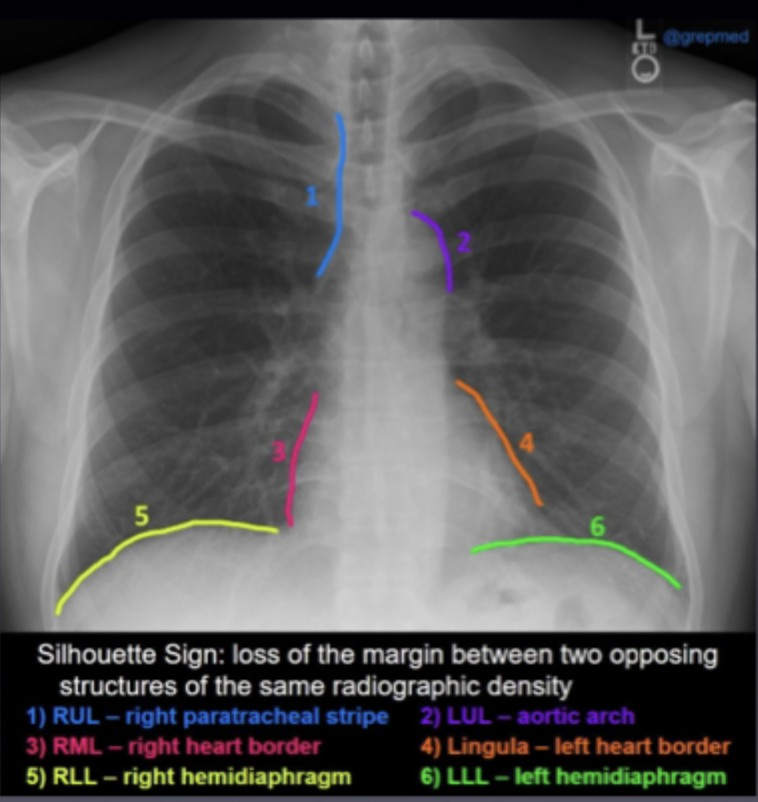

What is Silhouette sign ?

Occurs when two structures of similar radiographic density (like fluid and tissue) are adjacent, making their borders indistinguishable.

-helps identify potenial area of disease/abnormailty which obscures normal anatomical outlines

-indicates potential issues such as lung or pleural abnormalities; water density, infection, blood, pus etc

Which borders should be visible on a CXR ?

Silhouette sign obscures these

Where do different structures come into contact with the lung and create a silhouete